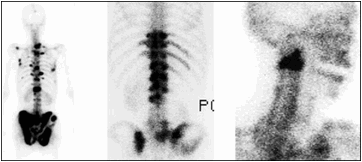

骨転移の診断:骨シンチグラフィ

従来、骨シンチグラフィは、感度は高い(異常の検出はよく出来る)が、特異度があまり高くない(異常がどのような原因で生じているのか分からない)検査と言われています。我々の施設では、パターン認識の要素を診断時に加味することにより成績が向上しています。その一端を紹介します。骨への転移と良性の変化を鑑別するポイントは、下記などです。

骨シンチグラフィの読影法

- 骨転移は骨髄で増殖するため骨の長軸に沿った形で拡がりやすい。一方、外傷は骨の長軸に垂直に現れやすい。

- 骨転移は骨の中に生じる。変性は関節面に生じる。

- 骨転移は病変の中央部が腫瘍に置き換わっていることが多いために中央部が欠損になり周囲に集積増加を認めることが多く、ドーナッツ型になります。他の原因によるものは、中央部の集積が高いことが多くあります。但し、前立腺がんによる骨転移など造骨型の骨転移は例外です。

- 骨転移は、左右非対称であることが多い。

- 骨転移の分布は、赤色骨髄の分布もしくはバトソン静脈叢の分布と一致することが多い。すなわち、体幹部および四肢の近位部に多い。

- 多発性であることが多い。